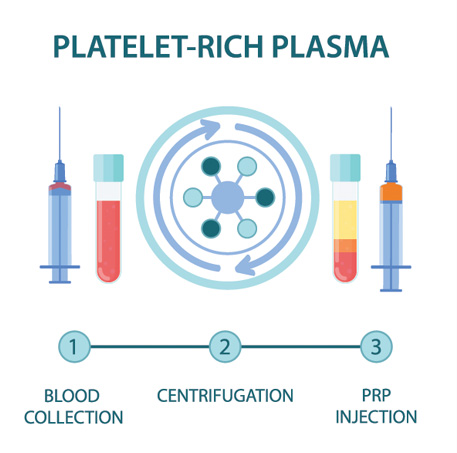

PRP is component of the patient’s own blood. It is rich in growth factors and other cells that signal an increased healing response to a damaged tissue. It is used to treat a variety of painful spine and musculoskeletal conditions.

Blood is drawn from a patient and then placed in a centrifuge for it to be “spun down.” This causes the different components of the blood to separate out in the vial. The PRP solution is then drawn up into a syringe and prepared to be injected at the site of the patient’s injury.

Once the PRP solution is created, the patient is positioned for the procedure. The skin is thoroughly cleaned and the target for the injection obtained with ultrasound or fluoroscopy (x-ray). Then, a numbing solution is injected at the skin and subcutaneous tissues for increased procedural comfort. Finally, under ultrasound or fluoroscopic (x-ray) guidance, the needle is guided to the injury site and the PRP solution is deposited.